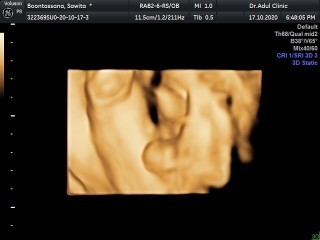

มาอวดภาพอัลตร้าซาวด์กันหน่อยแม่จ๋า 🤰🏻👼🏻 ชาย หรือ หญิง กันนะ?

ชายคับ

ชายค่ะ

ผู้ชาย

ลูกชาย

ชายจ้า